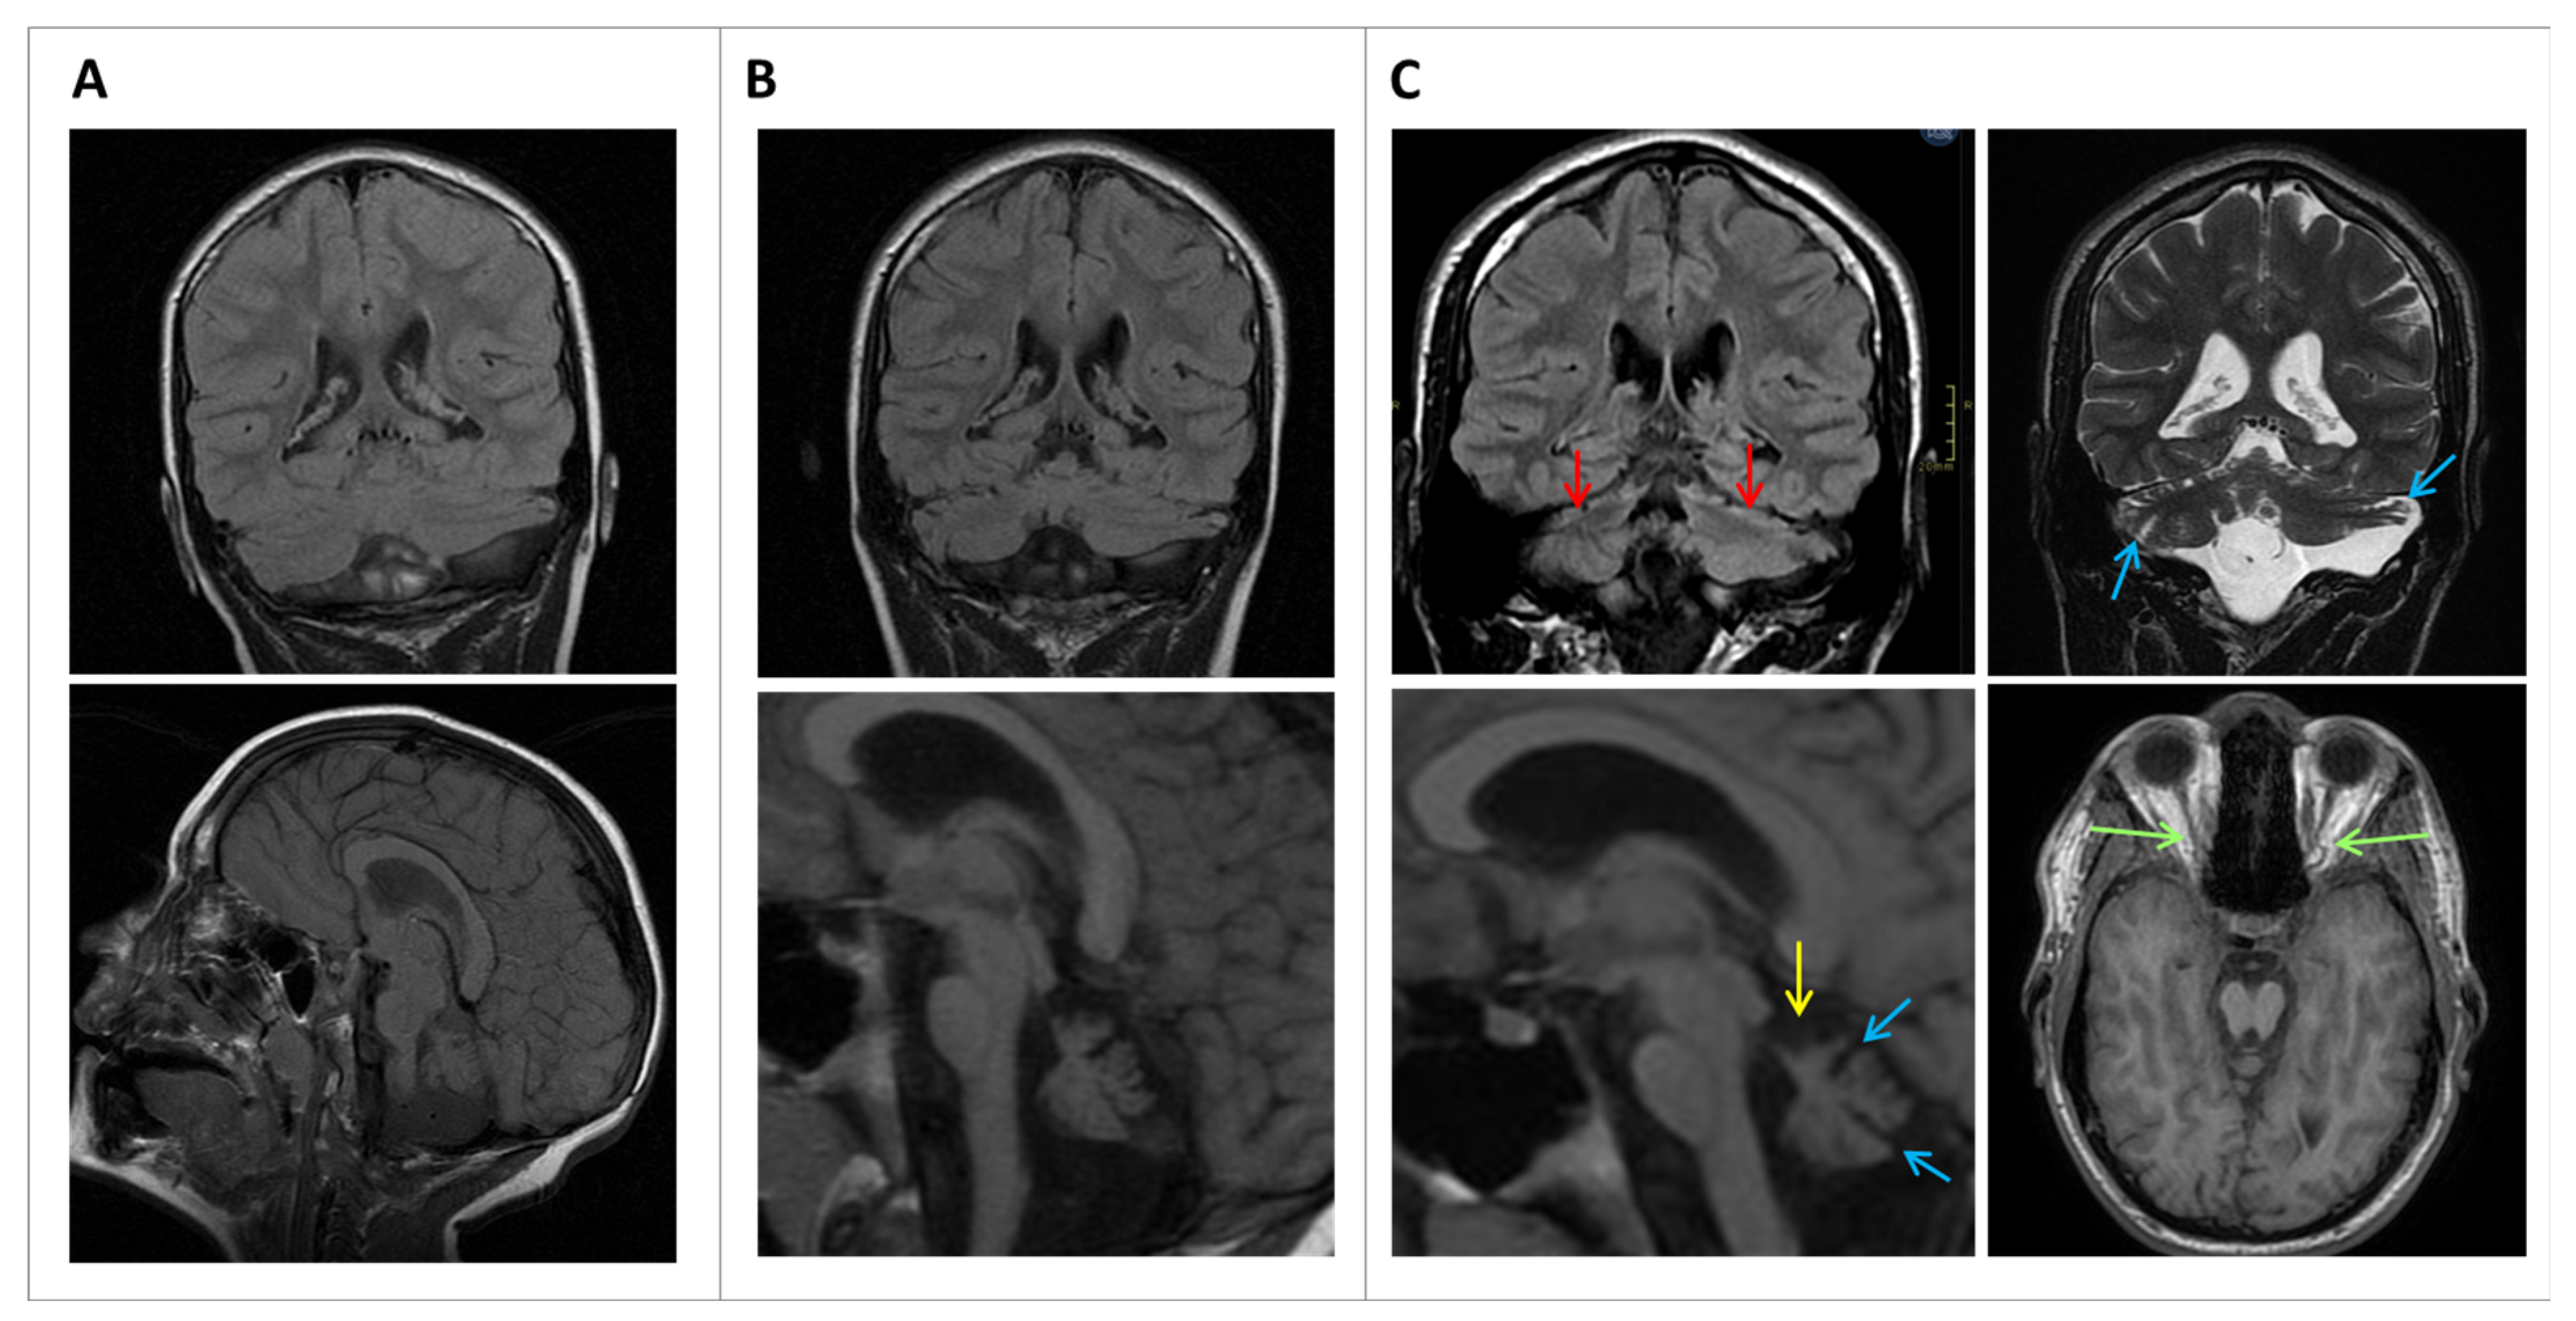

From early infancy, he showed global psychomotor deficits, affecting gross and fine motor skills, as well as language development retardation. He showed convergent strabismus. At the age of 4 years, he achieved independent walking, though he exhibited an ataxic, wide-based gait. He was referred to our hospital at the age of 6 years and first magnetic resonance imaging (MRI) showed pontine and cerebellar asymmetric hypoplasia, and an incipient increase in the cerebellar interfoliar spaces (Figure 1A). There was a ventricular enlargement without signs of hydrocephalus. By that age, he had attended special schooling due to moderate difficulties in understanding, speech difficulties using simple sentences, and motor clumsiness with an ataxic gait. In the physical exam, signs of spasticity, including increased deep tendon reflexes (DTR) and shortened Achilles’ tendons, were observed, as well as the previously mentioned convergent strabismus and horizontal nystagmus. A first nerve conduction study at the age of 10 years revealed mild neuroaxonopathy that remained stable during evolution. To improve his gait, he underwent orthopedic surgery on both Achilles’ tendons. Cranial MRIs at 10 and 16 years, respectively, showed pontocerebellar atrophy progression and optic nerve atrophy (Figure 1B,C), which were not previously detected in the neuroimaging and were not related to visual impairment. The supratentorial structures were normal, except for microcephaly, without any structural anatomical abnormalities, and the corpus callosum was normal. At age 13, a cognitive evaluation yielded an intelligence quotient score of 41 (Wechsler intelligence scale for children, WISC-IV). He never presented epilepsy or febrile seizures and, during evolution, there were no other organ or system comorbidities.

Figure 1. MRI at 6 years ((A): Coronal FLAIR T2, Sagittal FSE T1), at 10 years (B): Coronal FLAIR Details of image amplification have been notedT2, Sagittal FSE T1 amplified ×2), and 16 years of age (C): Coronal FLAIR T2, Coronal FSE T2, Sagittal FSE T1 amplified ×2.5, Axial 3D T1 SPGR). The initial MRI (A) shows the asymmetric volume of the cerebellar hemispheres, with the left hemisphere being smaller. There is also prominent inferior CSF space and atrophy of the vermis. No corpus callosum abnormalities are found. Follow-up MRIs (B,C) show progressive atrophy of both the cerebellum and the brainstem. There is a subtle widening of the cerebellar fissures (blue arrows) and more atrophy of the superior vermis (yellow arrow), denoting progressive atrophy. The pons is also slightly smaller. Differences are more evident when comparing (C) with (A). FLAIR T2 also shows thinning of the superior cerebellar cortex with high signal intensity (red arrows) that might correspond to cortical gliosis. Green arrows indicate optic nerve atrophy. Despite clinical microcephaly, no other structural abnormalities were found.